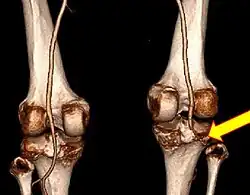

CT angiogram 3D reconstruction, posterior view showing a normal artery on the left, and occlusion to right popliteal artery as a result of a knee dislocation[10]